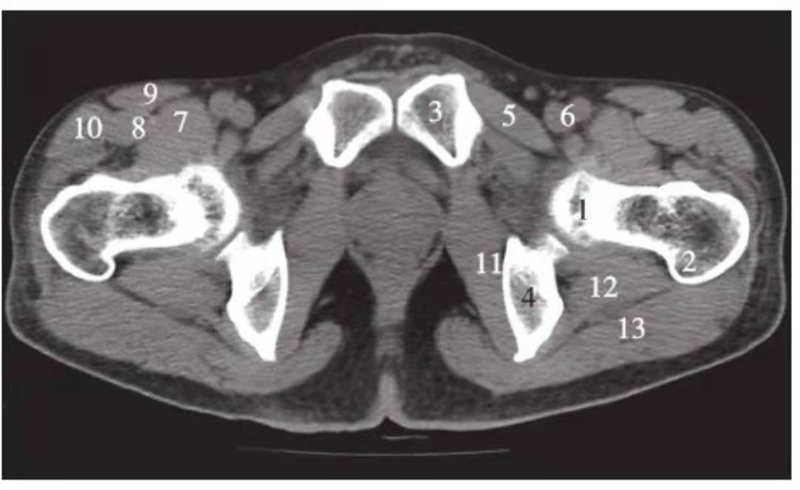

图2 股骨头凹上层面(骨窗)

1.股骨头;2.耻骨;3.坐骨;4.髋臼前唇;5.髋臼后唇;6.髋臼窝;7.尾骨

图3 股骨头凹层面(骨窗)

1.股骨头;2.星芒状结构;3.耻骨;4.坐骨;5.股骨头凹;6.髋臼窝;7.髋臼前唇;8.髋臼后唇

图4 股骨头凹下方层面(骨窗)

1.股骨头;2.髋臼前唇;3.髋臼后唇;4.前柱;5.后柱;6.髋臼前壁;7.髋臼后壁;8.髋臼窝;9.大转子;10.股骨头骨骺线;11.尾骨